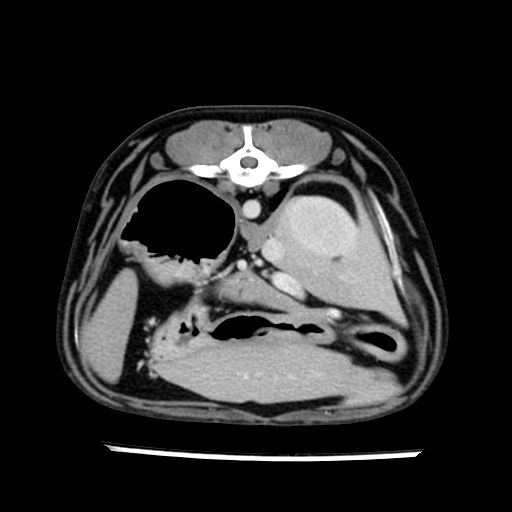

prescritto esame TAC

sequenza immagini limitata al fegato reni e surreni

le immagini ecografiche rispetto alla tac datano circa 7 mesi prima ,le surrenali sono normali nonostante il test acth sia risultato positivo .all’esame TAC dopo diversi mesi risultano aumentate armonicamente nel volume e si individua un forte sospetto di adenoma ipofisario .

sospetto adenoma ipofisario vs. meno probabilmente meningioma della base; intertiziopatia polmonare; lesione espansiva epatica, verosimilmente del lobo laterale sinistro, di sospetta natura neoplastica; lesioni spleniche di natura da definire; iperplasia/ipertrofia delle ghiandole surrenali, bilateralmente; vertebra di transizione del rachide toracico; tenosinovite cronica del muscolo bicipite brachiale di destra.

- Nessuna informazione diversa per quello che riguarda l’esame ecografico del fegato e la presa del contrasto si confermano le lesioni individuate e l’ipoenanchement in fase portale.

- la total body permette di escludere metastasi e di avvicinarsi all’interventistica

la tac dopo 7 mesi permette misure tridimensionali 5,2 x 9,2 x 4,5 cm (forma piu’ allungata )